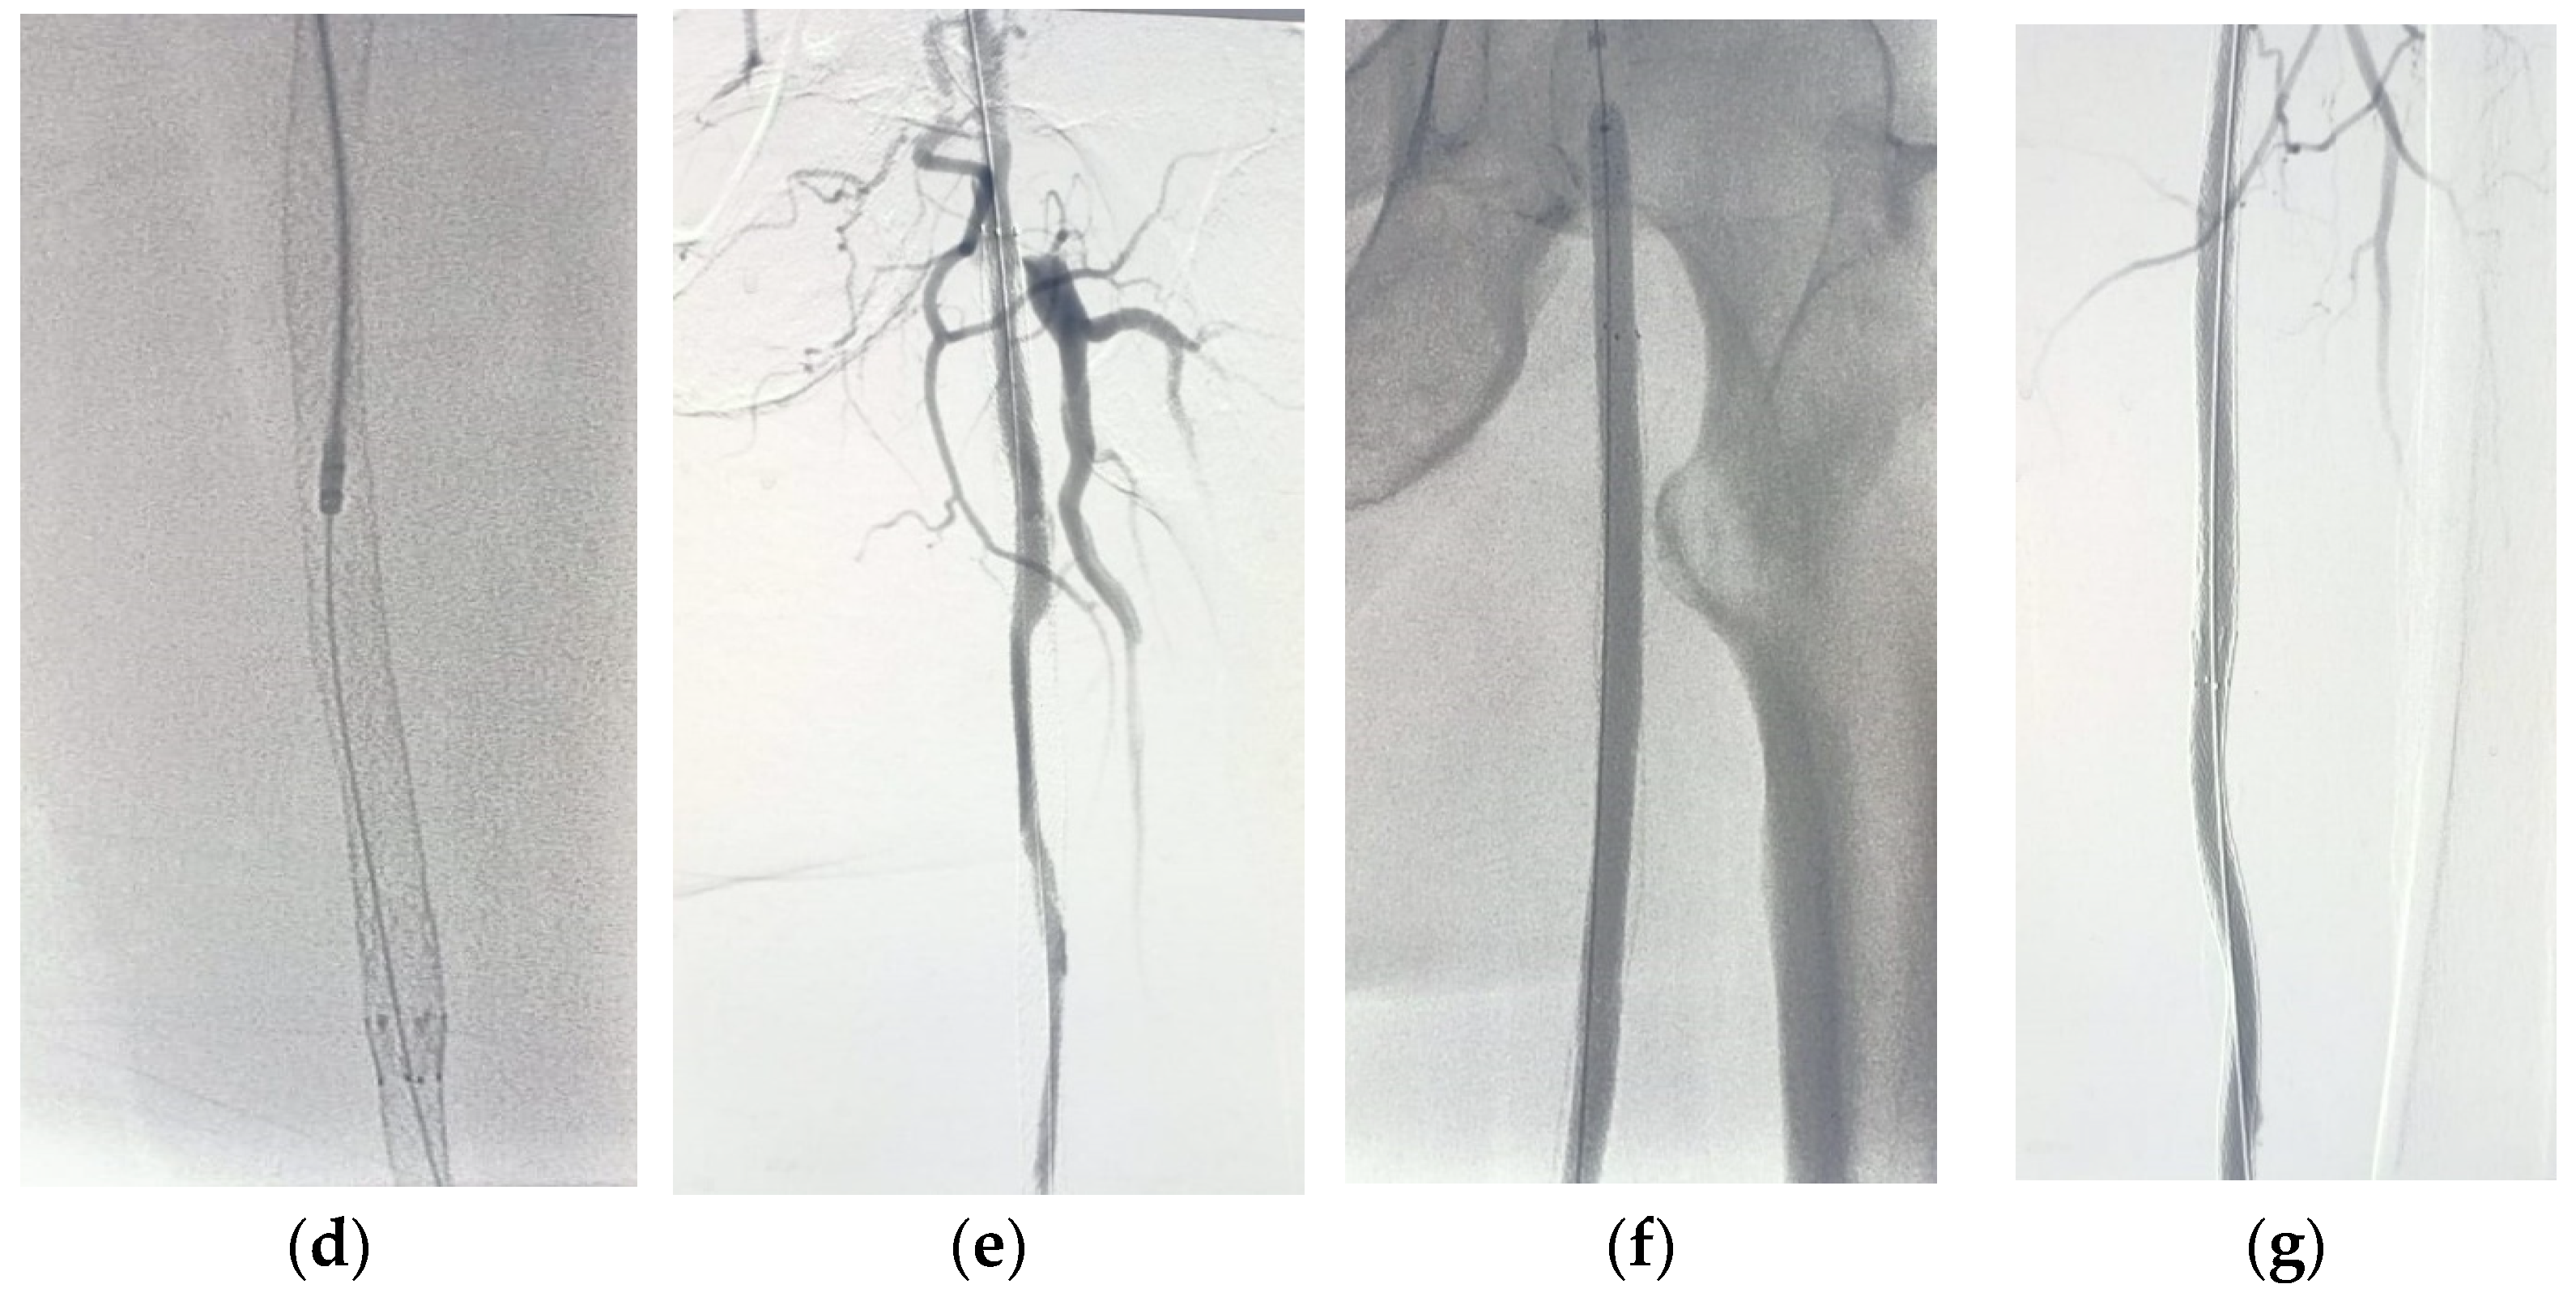

Figure 4. Diagnostic angiography showing LT SFA metal jacket ISR through cross-over antegrade access (ac); PMD using Rotarex® system (d,e); DCB angioplasty (f); completion angiography revealed successful revascularization (g) (in-stent restenosis (IRS), percutaneous mechanical debulking (PMD) and drug-coated balloon (DCB)).

The technical success was achieved in all patients 100%, whether treated by Rotarex + DCB (Figure 2, Figure 3, Figure 4 and Figure 5) or DCB alone (Figure 6), and all procedures were completed successfully.